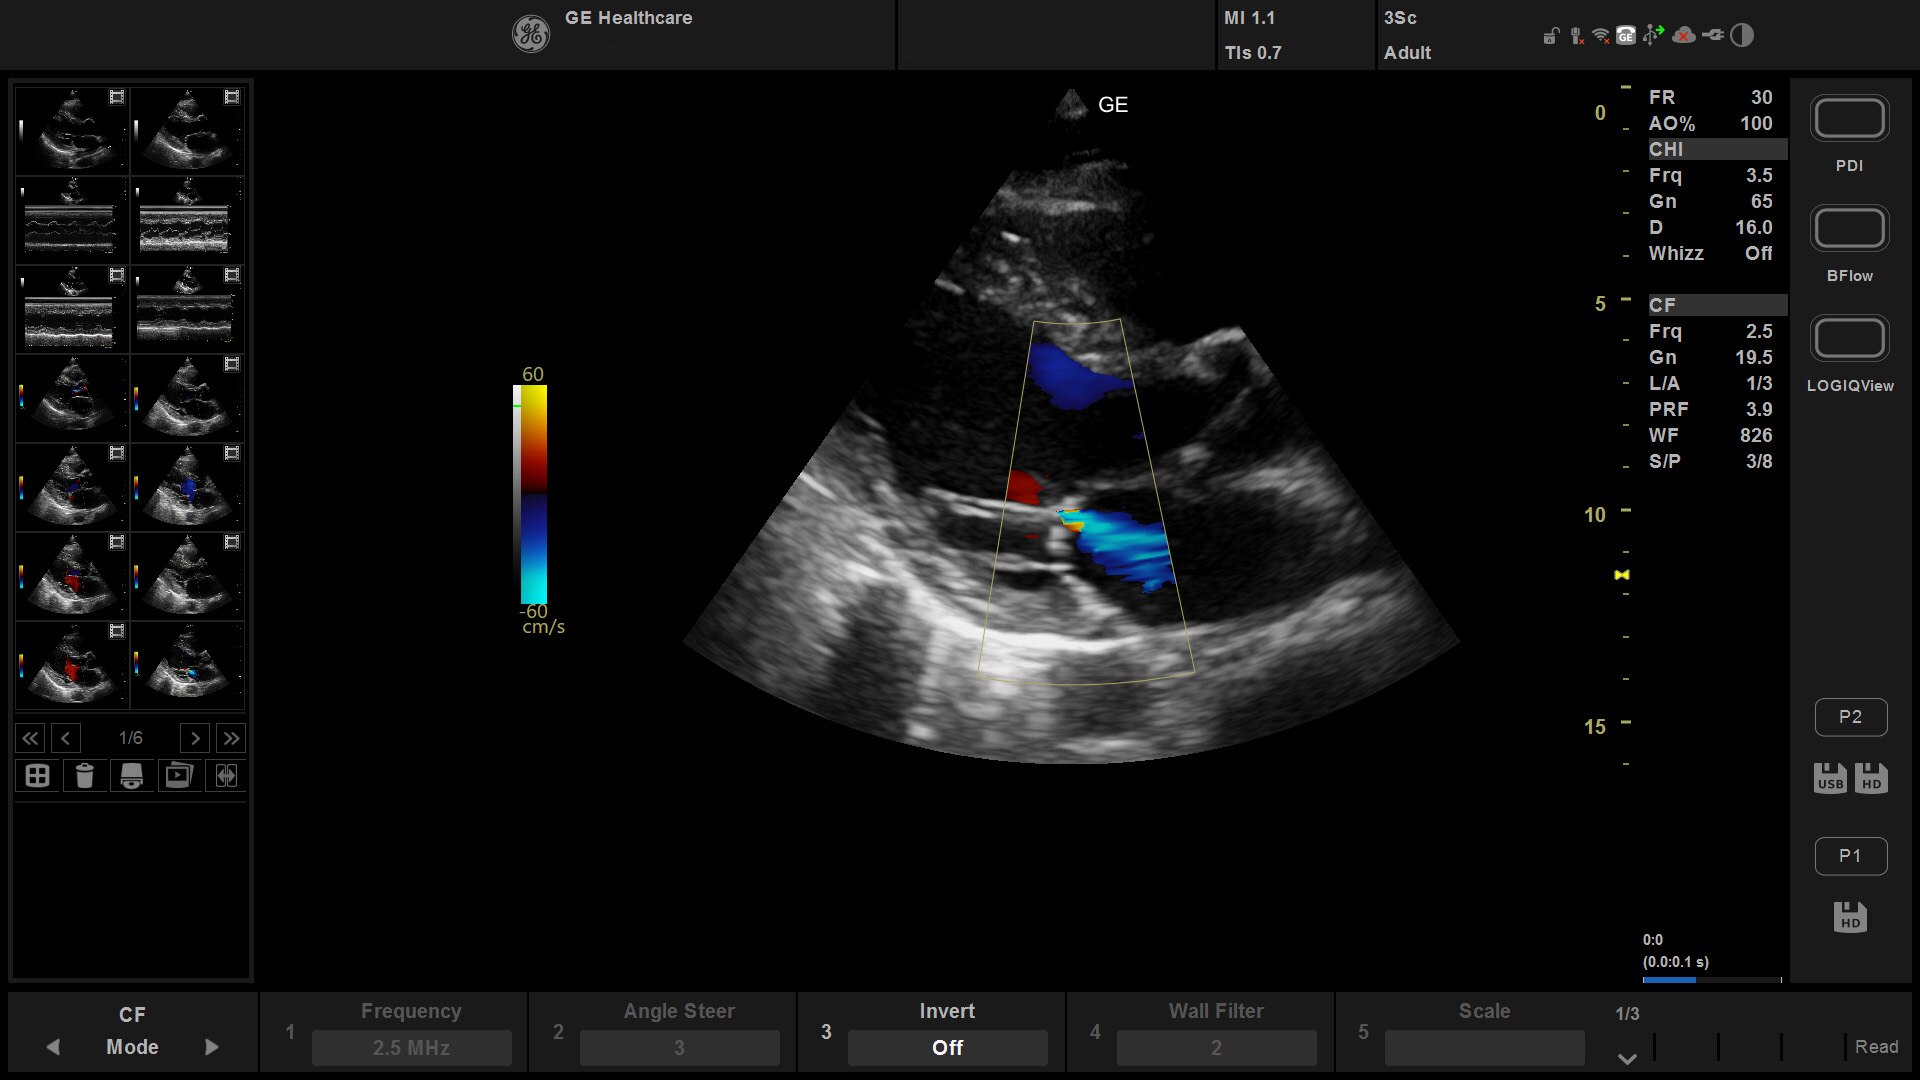

Suited for abdominal, small parts, cardiac, OB/GYN, vascular, and MSK exams

Versana Active delivers the imaging capability of a console in a hand-carried, lightweight package that enables you to actively take your system to your patients, on premises, or remote facilities. The reliable system brings the agility of a laptop unit with the capability for attaching to a cart. Adaptable to cover a broad range of everyday exams, it is easy to carry to clinics, offices, and beyond.

Versana Active features a wide range of advanced clinical applications and automated tools that simplify exams, streamline workflow, and enable fast, high-volume scanning to help you diagnose a wide spectrum of patient conditions.